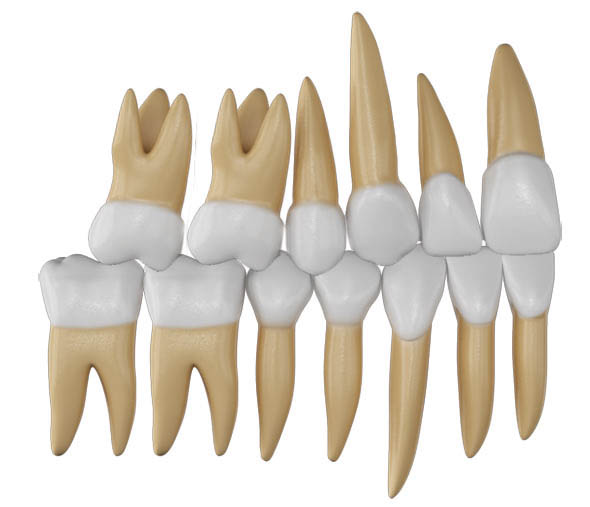

اگر قدامیهای پائین سایز بزرگتری داشته باشند دو حالت رخ میدهد یا پروترود میشوند (شکل 41-2) یا اگر روی همان قوس باشند حالت کرادینگ خواهند داشت (شکل 42-2).

از طرف دیگر اگر قدامیهای بالا سایز کوچکتری داشته باشند (مثلاً لترال بالا peg-shape باشد) در قوس کوچکتری قرار میگیرند (شکل 43-2).

در اول درمان، شاید کوچکی قدامیهای بالا یا بزرگی قدامیهای پائین خیلی مهم نباشد، اما وقتی به انتهای درمان میرسید و کانین بالا در پشت کانین پائین قرار میگیرد دیگر اورجت نرمال نخواهید داشت (شکل 44-2).

شکل 41-2: وقتی سایز قدامیهای پایین بزرگتر شود در قوس بزرگتری قرار میگیرند

شکل 42-2: انسیزورهای پایین بزرگتر از حد خود هستند اما پروترود نشدند، لذا حالت کرادینگ پیدا کردهاند